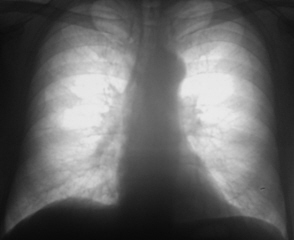

Пациент 76 лет жалоб не предъявляет. В 2006 году был направлен на профилактическую флюорографию.

Иллюстрация 1. Флюорограмма в прямой стандартной проекции. При анализе полученного изображения было констатировано усиление и обогащение легочного рисунка справа медио - базально. Было отмечено некоторое уплотнение тени правого корня в области тела. В остальном отмечены изменения возрастного характера.